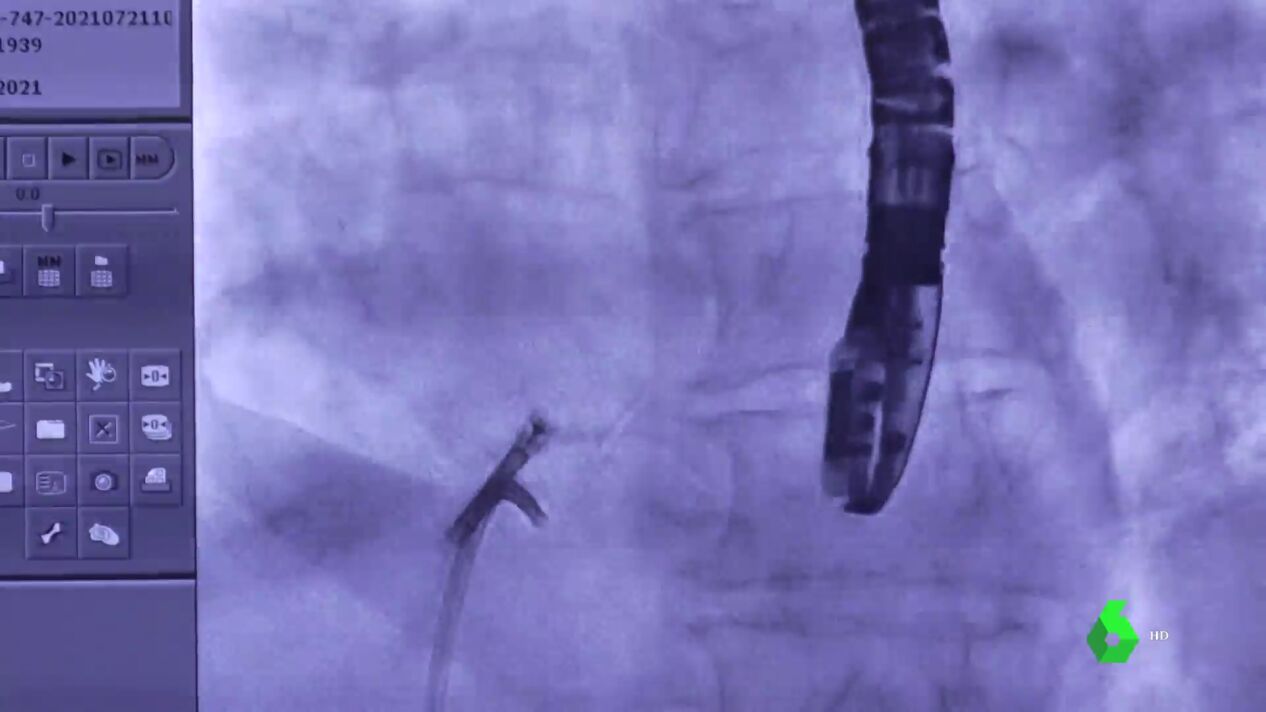

Este sistema (dispositivo V-LAP), desarrollado por una empresa de Israel, permite el seguimiento diario, a distancia y en directo, de la presión cardíaca en la aurícula izquierda del paciente, antes de que una excesiva incidencia derive en un encharcamiento de pulmones y aumente el riesgo de una parada fatal.

De momento se trata de un chip informativo, un pequeño ordenador insertado a través de una vena inguinal del enfermo, pero en un futuro no muy lejano tendrá también "una estrategia de tratamiento" mediante la apertura de una válvula de descarga entre las dos aurículas, aún en fase de investigación.